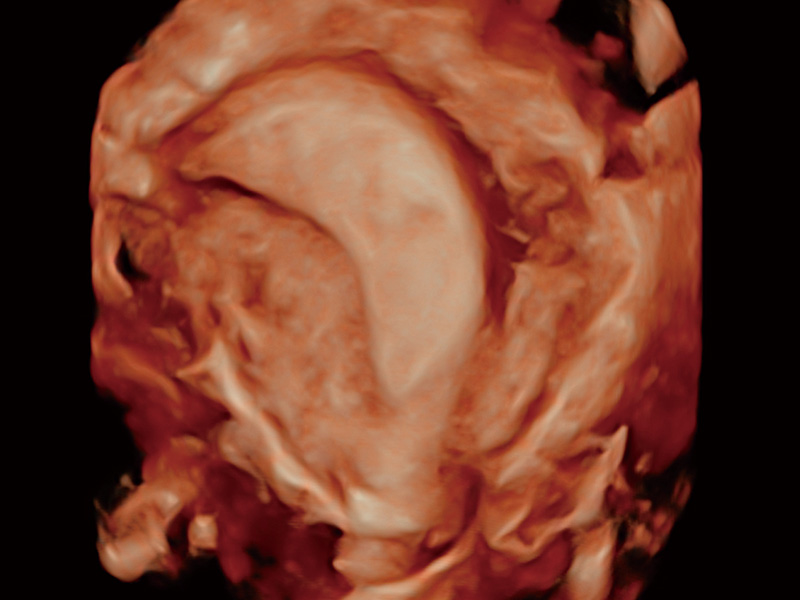

临床图

超声引导下胚胎移植

腔内三维成像技术获得显著提升,超大扇角在满足日常基础扫查的同时,支持卵泡自动测量及多种三维渲染模式,为您提供更多的诊断信息,尤其是在子宫畸形的诊断,内膜及肿瘤占位观测中起到了重要的作用。